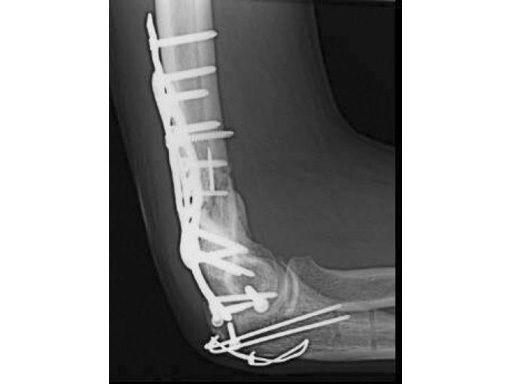

40-year-old man, 13-C3 fracture treated with DHP.